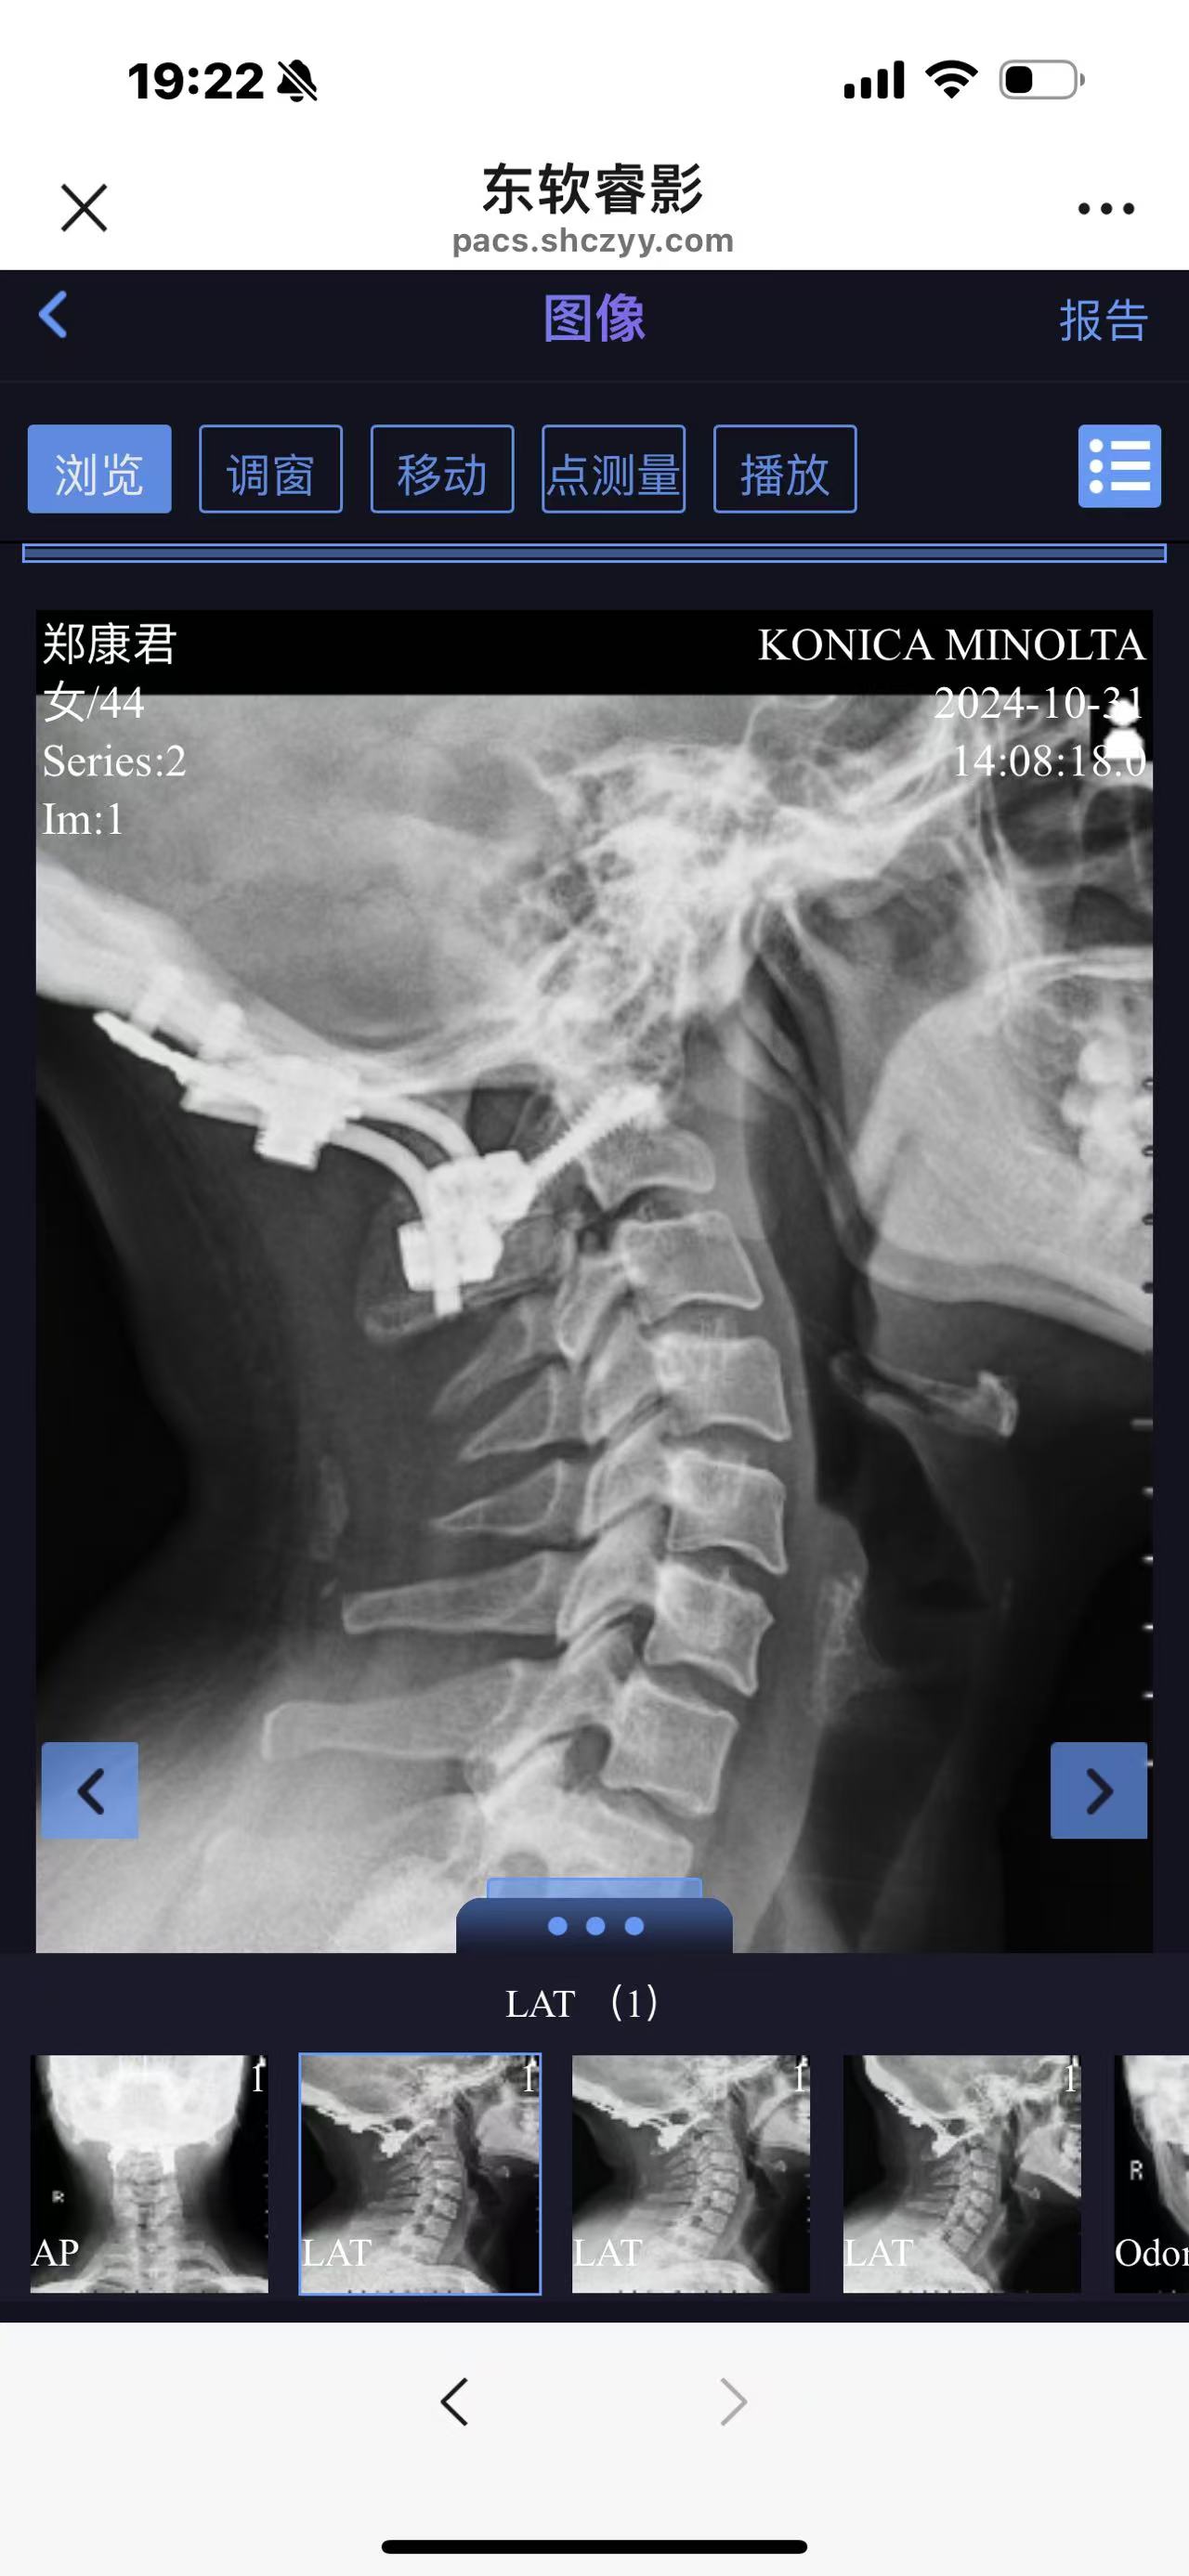

• 诊断:寰枢椎脱位

• 术后影像:

• 2024.10,复查,恢复良好。